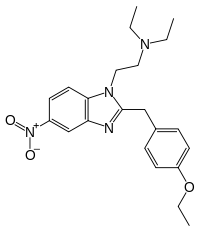

Benzimidazoles

Structures

| Benzimidazoles | ||||

|---|---|---|---|---|

|

|

|

|

|